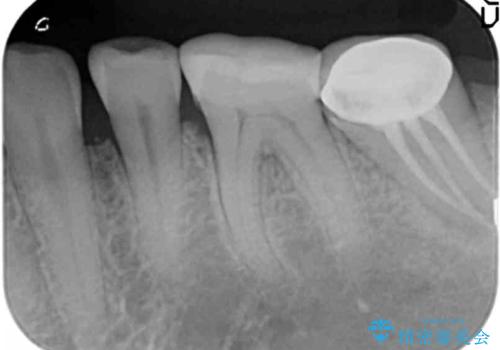

- 著しい歯ぎしりですり減ってしまった、奥歯のクラウンのやりかえを希望され来院されました。

このままの状態でクラウンのやりかえを行うと高さが低く安定の悪いクラウンとなってしまうため、事前に歯周外科手術を行い歯ぐきを下げることで安定性の高いクラウンを製作する治療計画としました。

高さの低いクラウンはセメントが漏出しやすく脱離しやすいだけでなく虫歯の再発の可能性も高まってしまいます。

長期にわたりに安定した環境に整えることで、長く使える可能性を高めることができます。